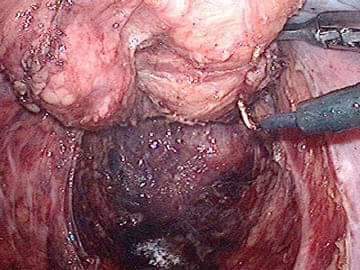

عمليات جراحية نوعية في مستشفى الملكة علياء العسكري…

أجرى فريق طبي جراحي عملية إزالة حصوة ذات حجم كبير من القناة المرارية الجامعة عن طريق تقنية المنظار لمريضة خمسينية.

وبين اختصاصي جراحة الكبد والقنوات المرارية الرائد الطبيب محمد الجبور، أن المريضة كانت تعاني من التهابات متكررة بالقناة الصفراوية الجامعة وبعد التشخيص تبين بأنها تعاني من انسداد في القنوات الصفراوية ناتج عن وجود حصوة كبيرة.

وأضاف الجبور بأن العملية اجريت بواسطة المنظار وهو الذي يعتبر نوعي في مثل هذه الحالات.

وأوضح رئيس قسم الجراحة بمستشفى الملكة علياء العسكري المقدم طبيب هيثم ربيحات، أن هذه العملية جاءت استكمالا للعمليات النوعية الأخرى التي تجرى في المستشفى عن طريق المنظار، مشيرا الى انه تم خلال الأسبوع الماضي استئصال ورم في المستقيم لمريض بواسطة المنظار.

وأضاف ربيحات أن هذه التقنية من شأنها مساعدة المرضى في العودة السريعة لحياتهم الطبيعية بعد العمليات الجراحية.

و أكد مدير مستشفى الملكة علياء العسكري العميد طبيب أحمد الخوالدة، أنه و منذ استئناف العمليات الجراحية في المستشفى تم إجراء ما يقارب المئة عملية جراحية تحت البنج العام خلال الثلاثة أسابيع الماضية في قسم الجراحة العامة. مشيراً للجهد المبذول من الطواقم الطبية الجراحية والتخديرية والتمريضية برئاسة مدير قسم التخدير بالمستشفى العميد طبيب رائد الصمادي.

إضافة لاستخدام تقنية المنظار بمختلف العمليات الجراحية من شأنه رفع سوية الخدمة الطبية المقدمة للمرضى في مستشفيات الخدمات الطبية الملكية.